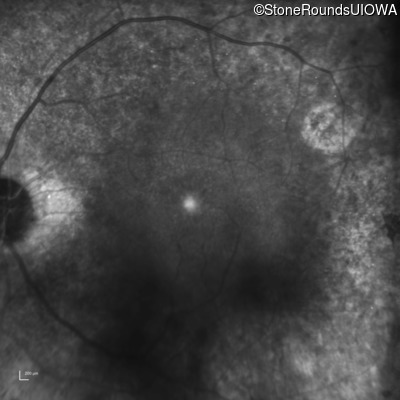

Infrared Fundus Photograph - Right - 20/32

Exemplar